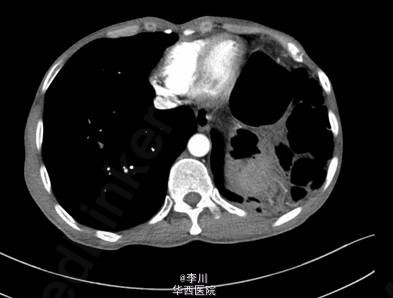

既往患者1+年前因摔跤撞伤腹部,于贵阳医学院行“脾切除+膈疝修补术”。查体左肺呼吸音减弱,可问及异常肠鸣音。CT提示:左侧膈面上抬、局部膈肌软组织似不连续,可见胃及部分肠管上移,膈疝?

在全麻下经左胸膈疝修补、胸膜粘连烙断、胸腔闭式引流术。术中发现:左膈肌外侧缺损约15cm×12cm大小,腹腔内网膜、胃及横结肠等组织疝入胸腔。网膜、胃、结肠组织与膈肌、胸壁片状粘连。左侧肺与胸壁广泛粘连。术后予抗炎、化痰、对症等治疗后好转。